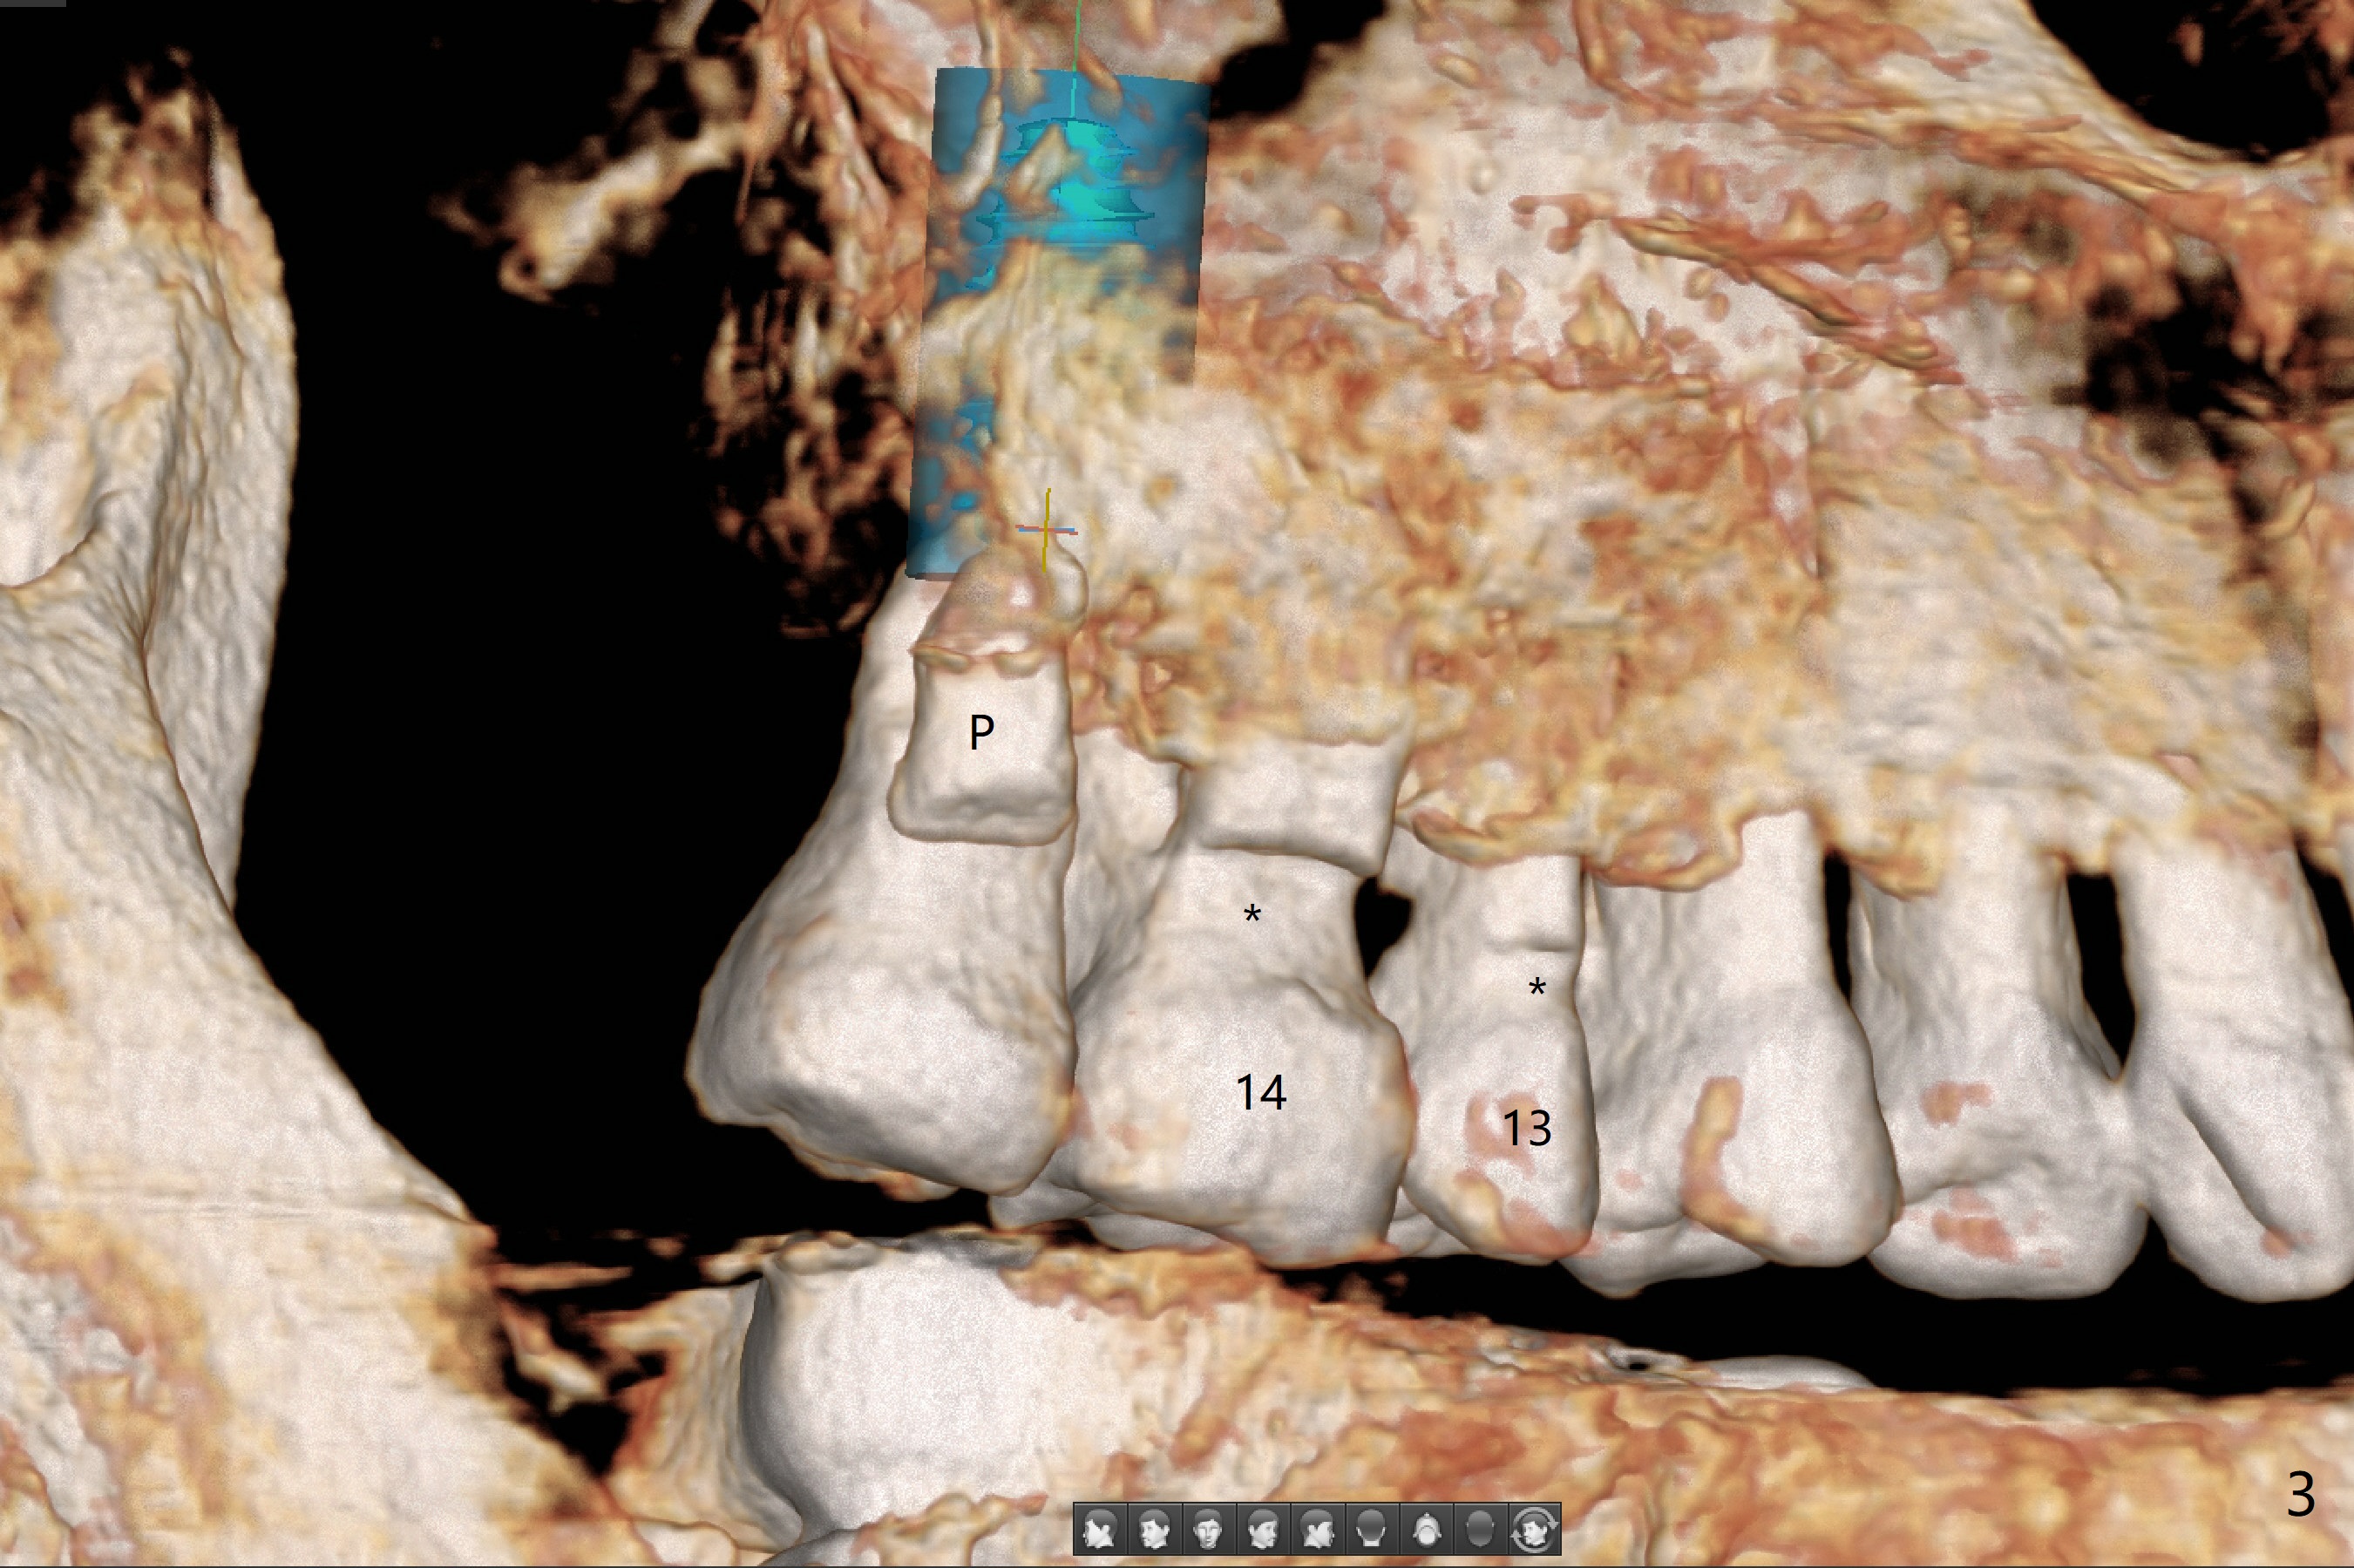

A 79-year-old woman returns to clinic suddenly, requesting extraction of the tooth #31 with mobility III (3 years 8 months post cementation for #25; 2 years 6 months post cementation for #18-20; Fig.4). An immediate implant is planned (Fig.1). After extraction, the large socket has relatively small opening, seemingly easy to keep bone graft in place. The immediate implant with 2-3 mm native bone may not have primary stability, most likely losing its ability to hold bone graft. Therefore socket preservation is conducted at #31. In contrast there is enough bone for an immediate implant at #15 (Fig.2) with palatal root fracture (Fig.3 (palatal view)).